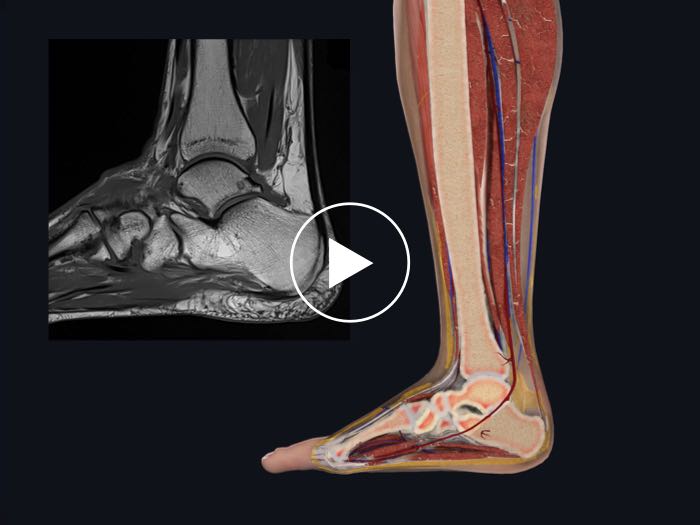

Cross-Sections

Take transverse cross-sections through any structure to learn about it in context and compare with MRIs

Radiology

Explore a suite of radiology images and correlate their structures to the 3D model